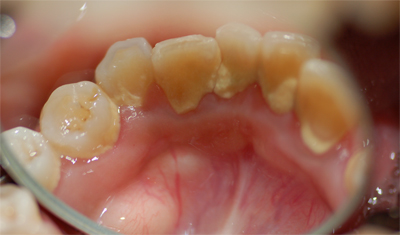

ひどい虫歯(C4)

C4 歯根のみ 初期において無症状だが、ばい菌が歯の神経のあった管を通じて生体に及ぶと、歯の根の先の部分が腫れたり、膿がでてきたりする。 初期、神経のあった管をきれいにして、管を密閉させる薬材をいれる。

その後、歯を補強(支台築造)し補綴処置(かぶせ物)をする。

末期、抜歯。